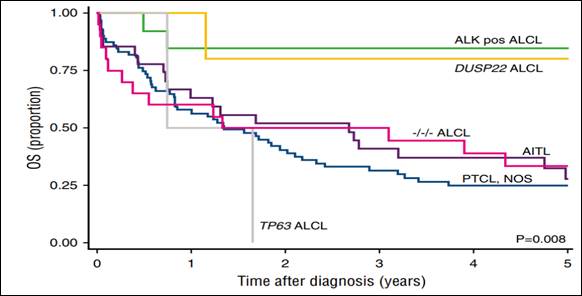

Si este paciente se presentase hoy a nuestro servicio, tendría nuevas posibilidades. Una, es la posibilidad de caracterizar a los pacientes con LNH-T anaplásico ALK - según su riesgo molecular, realizando estudios de DUSPP22 y TP63. Entendiendo que los pacientes DUSPP22 + tiene un SG a 5 años superior, cercana al 80%, y en pacientes TP63+, ésta es menor al 2% (Figura 3)(9).

Figura 3. Sobrevida global de acuerdo al perfil molecular